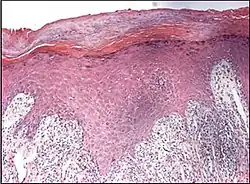

Interface dermatitis with lichenoid inflammation

| Generally/Not otherwise specified | Typical findings:[2]

||

| Lichen planus | Irregular epidermal hyperplasia with a jagged “sawtooth” appearance, compact hyperkeratosis or orthokeratosis, foci of wedge-shaped hypergranulosis, basilar vacuolar degeneration, slight spongiosis in the spinous layer, and squamatization. The dermal papillae between the elongated rete ridges are frequently dome shaped. Necrotic keratinocytes can be observed in the basal layer of the epidermis and at the dermal-epidermal junction. Eosinophilic remnants of anucleate apoptotic basal cells may also be found in the dermis and are referred to as “colloid or civatte bodies”. Whickham striae are usually seen in the areas of hypergranulosis. Vacuolar degeneration at the basal layer may be noted leading to focal subepidermal clefts (Max Joseph spaces). Squamatization occurs as a result of maturation and flattening of cells in the basal layer. It happens in areas of marked hypergranulosis with prominence of the sawtooth pattern of rete ridges. Wedge-shaped hypergranulosis can occur in the eccrine ducts (acrosyringia) or hair follicles (acrotrichia). In the hypertrophic subtype, the associated hyperkeratosis, parakeratosis, hypergranulosis, papillomatosis, acanthosis, and hyperplasia markedly increased with thicker collagen bundles forming in the dermis. Moreover, the rete ridges are more elongated and rounded as opposed to the typical sawtooth pattern. In atrophic LP, loss of the rete ridges and dermal fibrosis is prominent. In vesiculobullous LP, the disease progression is quicker. Hence, some of the distinctive features such as hyperkeratosis, hypergranulosis, or dense lymphocytic dermal-epidermal infiltrate may not be present. LP lesion may resolve with residual hyperpigmentation caused by a persistent increase in the number of melanophages in the papillary dermis.[9] | ![]() |

|

| Lichenoid drug reaction |

Can virtually be indistinguishable from cutaneous LP both clinically and histopathologically.

![]() |

Interface dermatitis with lichenoid inflammation, not otherwise specified, can be caused by lichen planus-like keratosis, lichenoid actinic keratosis, lichenoid lupus erythematosus, lichenoid GVHD (chronic GVHD), pigmented purpuric dermatosis, pityriasis rosea, and pityriasis lichenoides chronica.[2] Unusual conditions that can be associated with a lichenoid inflammatory cell infiltrate are HIV dermatitis, syphilis, mycosis fungoides, urticaria pigmentosa, and post-inflammatory hyperpigmentation.[2] In cases of post-inflammatory hyperpigmentation, it is important to exclude potentially harmful mimics such as a regressed melanocytic lesion or lichenoid pigmented actinic keratosis.[2]